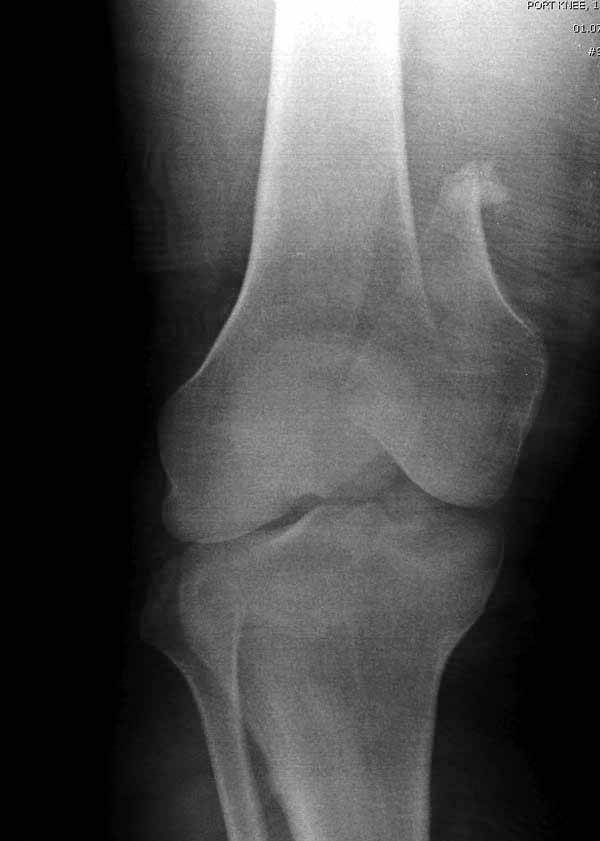

Коллеги, извиняюсь за задержку с результатом. Через медиальную артротомию обнажили н/3 бедра, отрепонировали внутренний мыщелок, затем по нему сопоставили суставную поверхность бедра с латеральным мыщелком.

Больная выписана в ортезе с регулируемым углом сгибания в колене, с рекомендациями через 3 нед. удалить спицы и начать разрабатывать сустав.

По прямому снимку репозиция удалось, поздравляю! А с латеральной стороны подозрение на флексионный компонент латерального мыщелка остается, а снимок получился косым, надо было бы повторить.

Выбор имплантов не совсем удачный, подкожно выступающие болты в мыщелках вскоре могут привести к проблемам. Вместо солитарной фиксации болтом-стяжкой дистально можно было бы добавить пару винтов, которые создали бы ротационную стабильность и межфрагментарную компрессию.

Возможно, есть скрытый замысел, неочевидный для нас - не понятны латерально оставленные спицы. Спицы возможный очаг вторичного осложнения, и, тем более у взрослых, тонкие спицы не создают адекватную фиксацию.

Djoldas,скрытого смысла в спицах нет. Без них латеральный мыщелок получается фиксированным только к медиальному, который, в свою очередь, фиксирован к проксимальному отломку. Соответственно латеральный мыщелок не фиксирован к бедру. Спицами мы попытались создать какую-никакую-стабильность латерального мыщелка относительно проксимального отломка бедра.

Болт-стяжка, на мой взгляд, создает не меньшую межфрагментарную компрессию чем винты. Не понял относительно ротационной стабильности винтов.